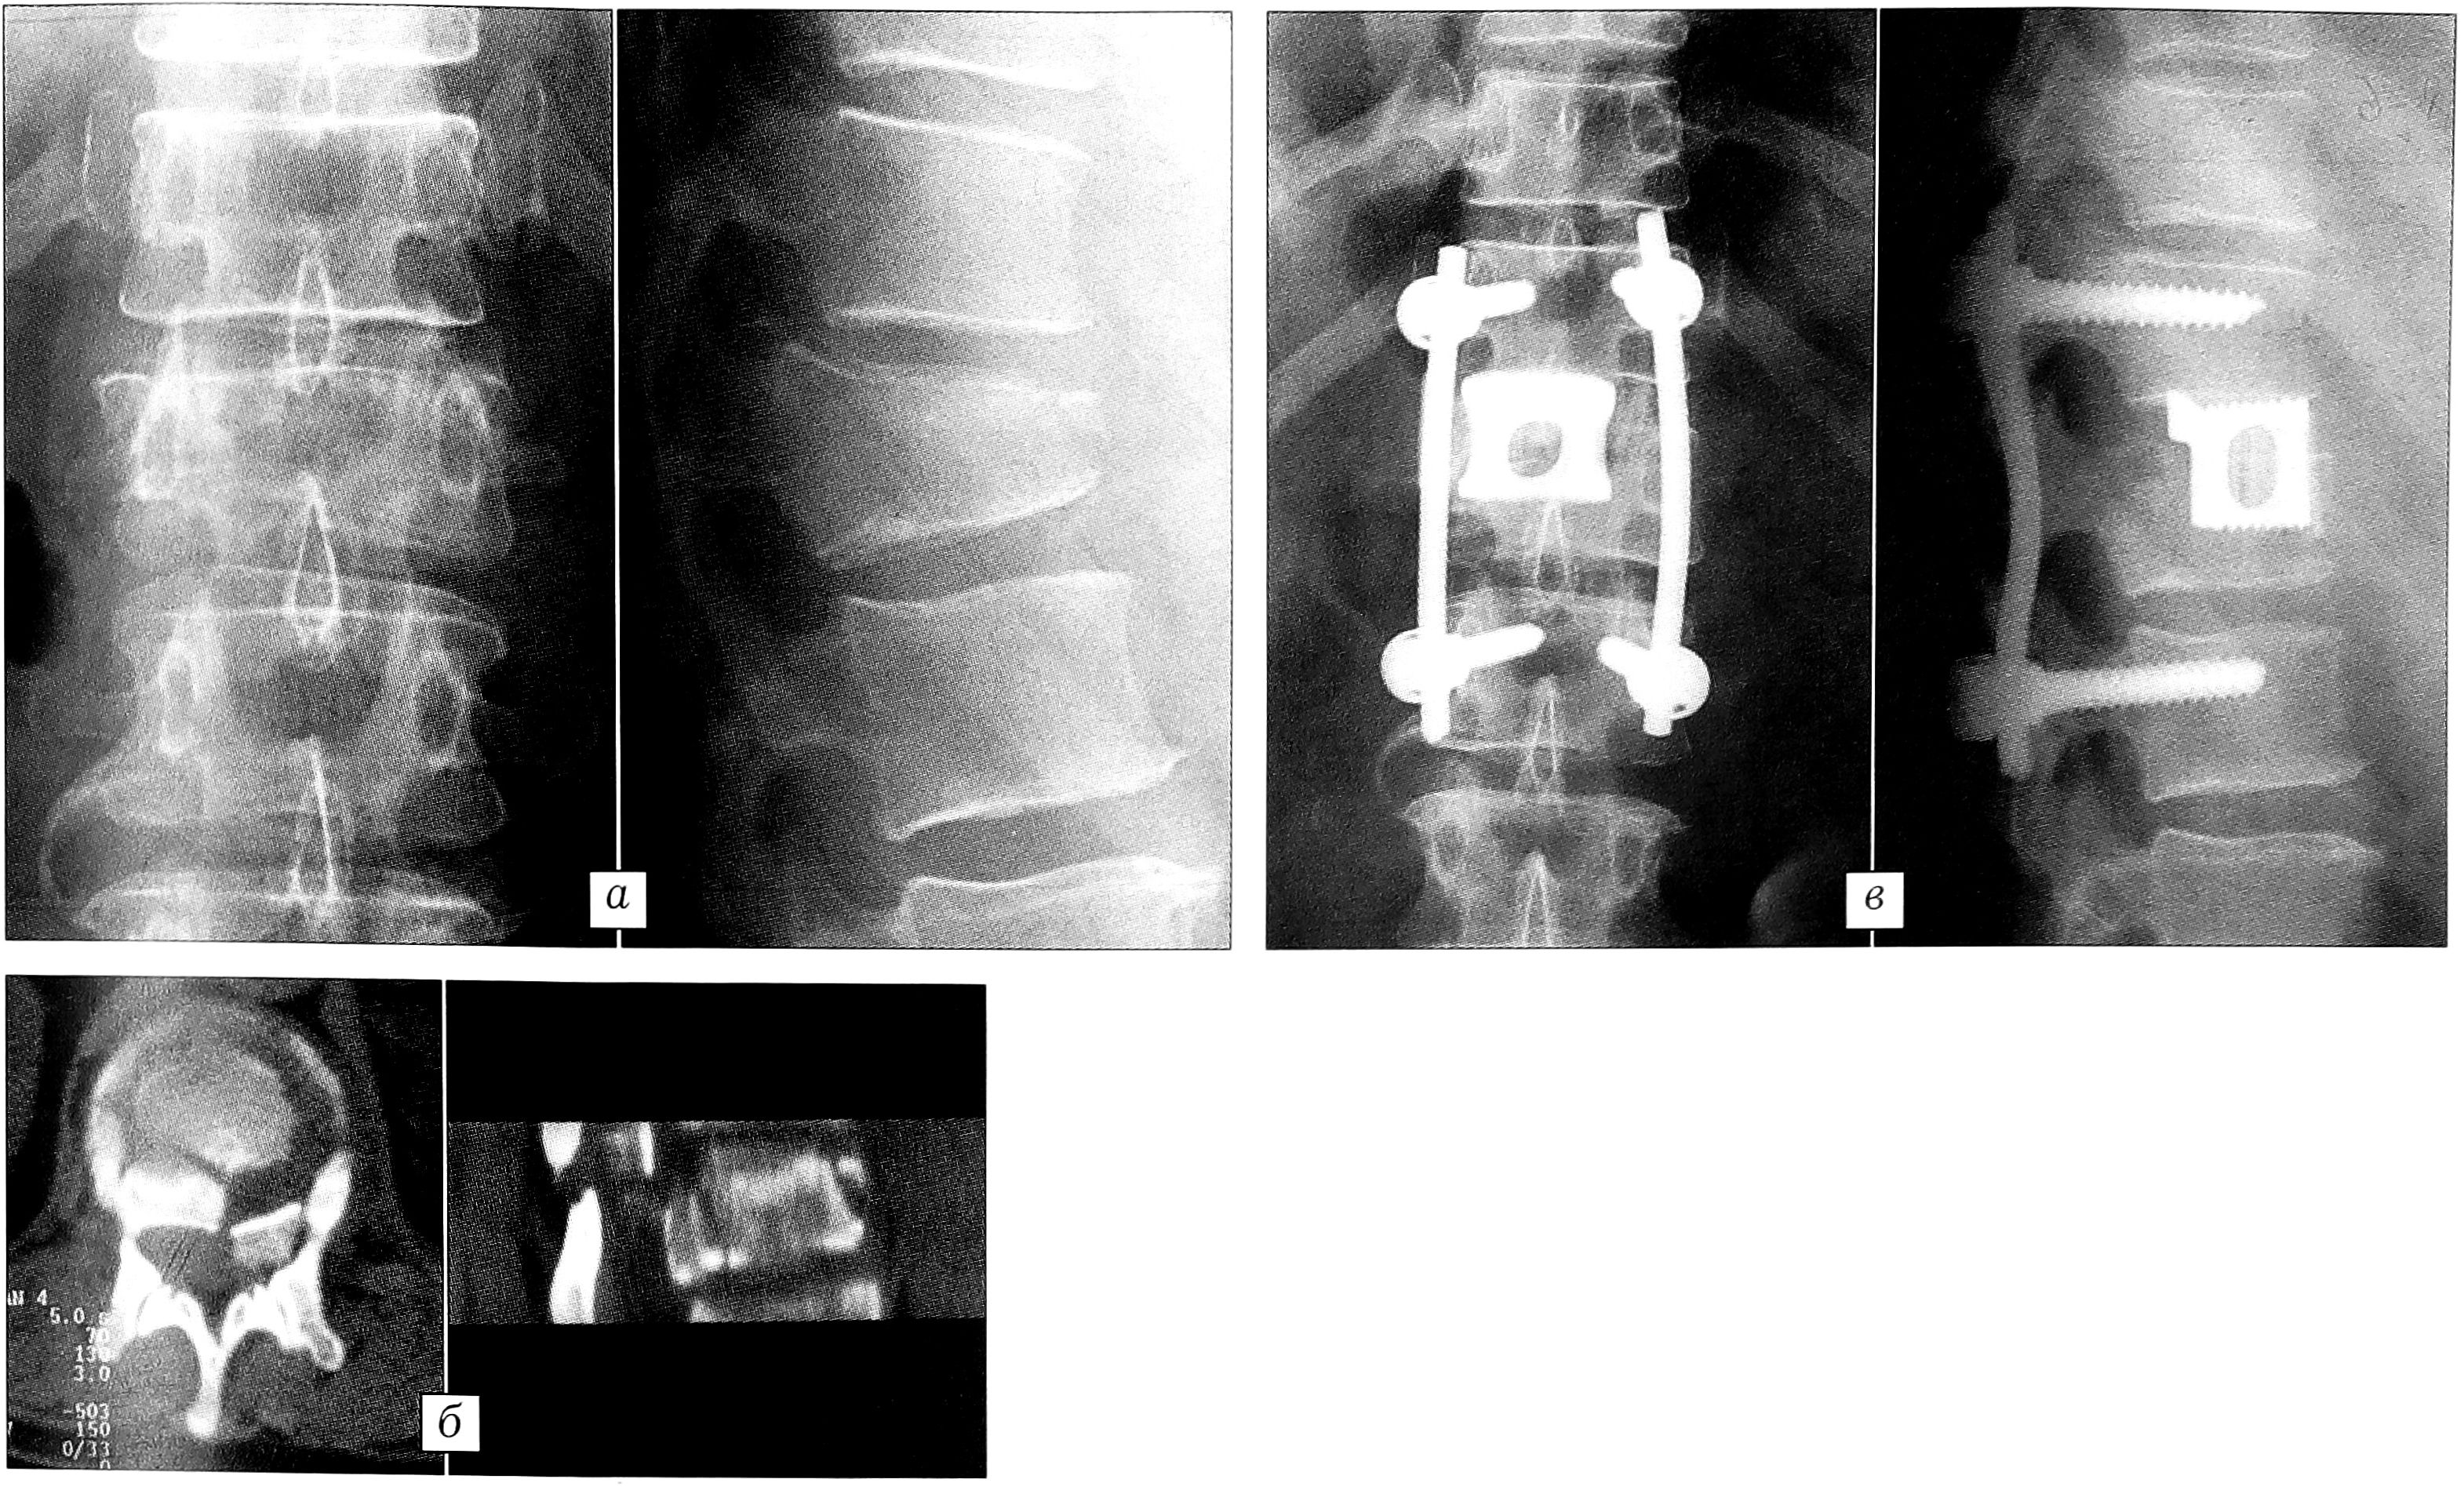

Стабильные проникающие компрессионные, взрывные неполные и полные переломы тел позвонков, тип А. Такие стабильные переломы, особенно с выраженной осевой деформацией и дислокацией дорсального фрагмента в позвоночный канал без одновременного разрушения средней и дорсальной колонн, требуют оперативного лечения. Консервативные методы лечения, дорсальная фиксация различными конструкциями, применяемые многими травматологами, как правило, не устраняют посттравматическую деформацию и не обеспечивают благоприятного исхода. Методом выбора при проникающих компрессионных, взрывных стабильных переломах тел позвонков (типа А) является корригирующий вентральный спондилодез, при необходимости с передней декомпрессией и, в зависимости от повреждения одного или двух сегментов, с моносегментарной (рис. 1) или бисегментарной (рис. 2) эндофиксацией. Характер, обем операции, особенности коррекции деформации сломанного позвонка, передней декомпрессии, размеры моно-, бисегментарного коронарного эндофиксатора определяются при предоперационном планировании по данным рентгенографии, компьютерной томографии. Во время операции полностью исправляется осевая деформация и восстанавливается высота травмированного позвоночного сегмента (см. рис. 1, в и рис. 2, в).

Рис. 1. Больной С. 47 лет. а — рентгенограммы до операции: неполный взрывной перелом тела L1 позвонка, кифоз 24°; б — стереотомограммы до операции: деформация позвоночного канала, каудальная часть тела позвонка не повреждена; в — рентгенограммы через 1 год после корригирующего корпородеза, аутопластики и моносегментарной эндофиксации.

Оптимальный срок проведения операции — первые 7-10 дней после травмы. Используемые нами оригинальные коронарные эндофиксаторы (пат. 2133596 РФ, регистрационное удостоверение № 29/12020201/2886-01 в Государственном реестре медицинских изделий) создают после коррекции стабильную фиксацию поврежденного сегмента в течение всего периода формирования межтелового костного блока, предотвращая рецидив деформации позвоночника. При этом продолжительность постельного режима после операции сокращается до 2-3 нед, пациенты избавляются от длительной иммобилизации корсетом, обеспечивается возможность более функционального полноценного восстановительного лечения.